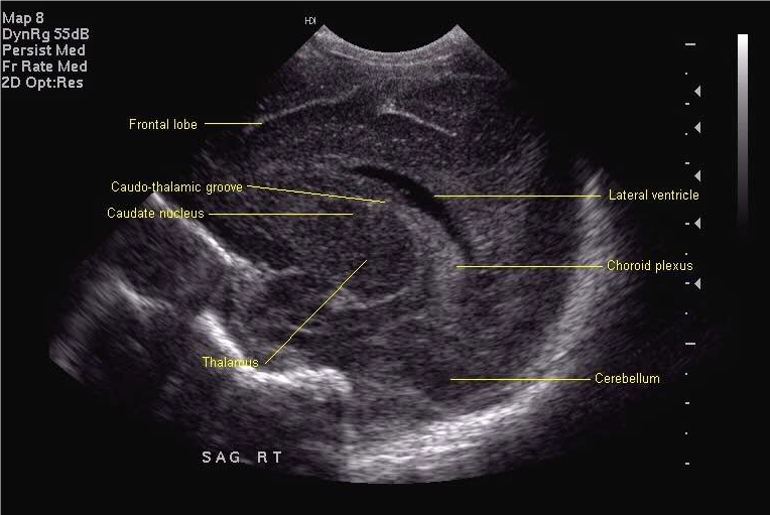

All scan results should be discussed with parents and, unless normal, this should be done by a member of the senior medical team. Although standard views for examination and hard copy print out are shown below, it is good practice to examine the peripheries of the brain including extreme lateral sagittal views, extreme anterior and posterior coronal views.

Midline Sagittal

Lateral sagittal (to be labelled "left" or "right")